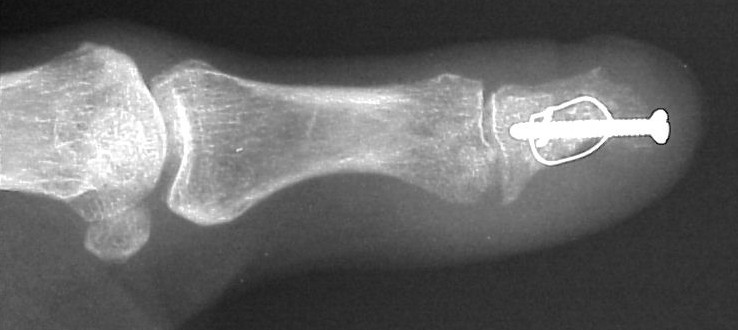

Exploration revealed no discrete  tumor, and a nondiagnostic frozen section. Because of diagnostic uncertainty and in order to avoid intraoperative cross contamination, a cancellous freeze dried allograft was used as a terminal graft:

Click for larger image

This incorporated, with some terminal resorption: